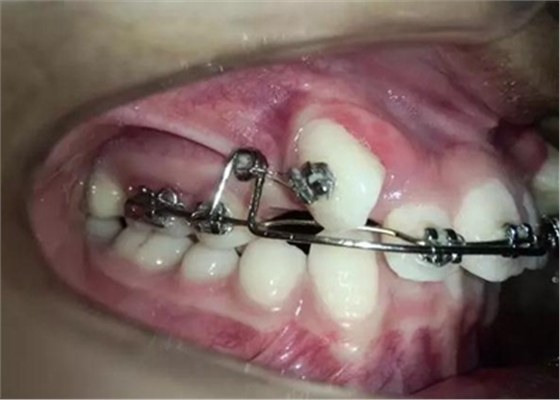

那好吧還是采用輔弓增加支抗,經(jīng)濟適用,也便與操作,0.8不銹鋼絲彎制,進行熱處理,增加其彈力。

牽引了三四個月尖牙終于長出來了,也遠離了側(cè)切牙

當尖牙到達了指定位置后,又采用了主弓絲和附弓絲,主弓絲采用了不銹鋼絲方絲,有效的避免了反作用力引起相鄰的牙齒出現(xiàn)小開合, 維護牙弓形態(tài)。

主弓絲和輔弓絲的結(jié)合使用,可以有效避免出現(xiàn)小開合,同志們一定要注意啊!

一個月后尖牙下來很多,

加上垂直牽引,尖牙下來的更快了